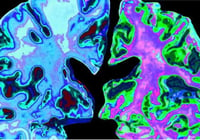

El ADN de humanos antiguos está proporcionando algunas pistas vitales sobre la aparición de la esclerosis múltiple y otras enfermedades neurodegenerativas devastadoras…